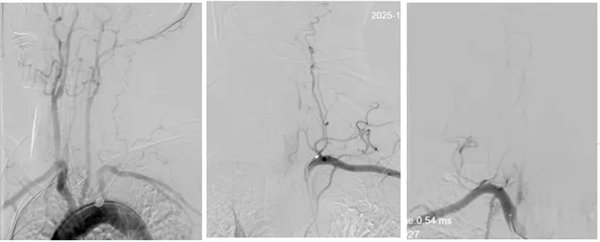

為最大程度搶救腦細(xì)胞,縮短腦組織供血恢復(fù)間隔,神經(jīng)內(nèi)三科卒中救治團(tuán)隊(duì)立即啟動(dòng)綠色通道實(shí)施介入取栓治療,麻醉醫(yī)師迅速抵達(dá)導(dǎo)管室,神經(jīng)內(nèi)三科主任席聰對(duì)患者進(jìn)行急診血管造影后發(fā)現(xiàn):患者左椎動(dòng)脈起始段閉塞,右椎動(dòng)脈起始部次全閉塞。

術(shù)中,介入團(tuán)隊(duì)精準(zhǔn)定位血管閉塞部位,通過(guò)微導(dǎo)絲“探路”聯(lián)合球囊擴(kuò)張技術(shù)開(kāi)通右側(cè)椎動(dòng)脈開(kāi)口,造影椎開(kāi)口殘余狹窄60%。基底動(dòng)脈血栓形成,基底動(dòng)脈管腔狹窄55%,基底動(dòng)脈尖堵塞,右側(cè)大腦后動(dòng)脈及小腦上動(dòng)脈未見(jiàn)顯影,左側(cè)大腦后動(dòng)脈P3以遠(yuǎn)閉塞。